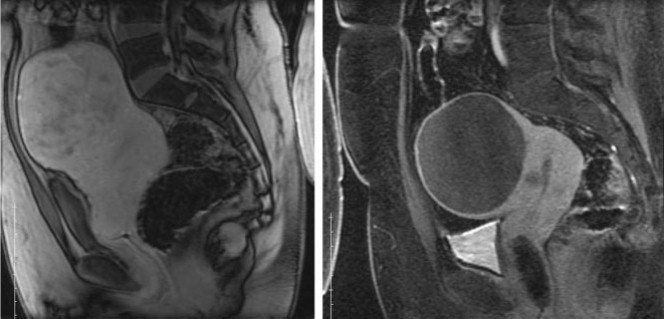

图示:介入栓塞前后的对比,术前血供丰富的肌瘤已经完全缺血坏死。